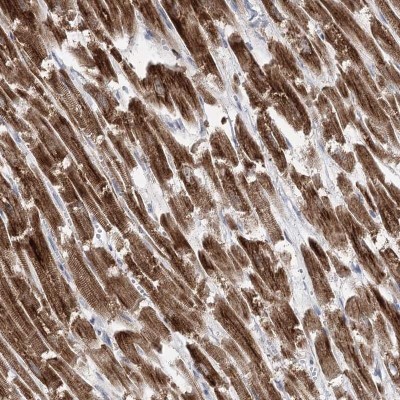

- Immunohistochemistry-Paraffin: Pyruvate Dehydrogenase E1 beta subunit Antibody [NBP1-87421] - Staining of human cerebral cortex, heart muscle, kidney and pancreas using Anti-Pyruvate Dehydrogenase E1 beta subunit antibody NBP1-87421 (A) shows similar protein distribution across tissues to independent antibody NBP2-38327 (B).